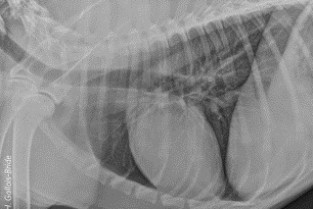

Le GEIM vous propose une séance de travaux pratiques de radiographies sur le thorax. Tous les aspects sont abordés sous la forme de TP de lecture de radiographies numériques sur station de travail Osirix sur Mac (3 vétérinaires maximum/ordinateur).

- adopter une méthodologie pour interpréter des radiographies thoraciques chez les carnivores domestiques

- décrire la radioanatomie du thorax chez les Carnivores domestiques